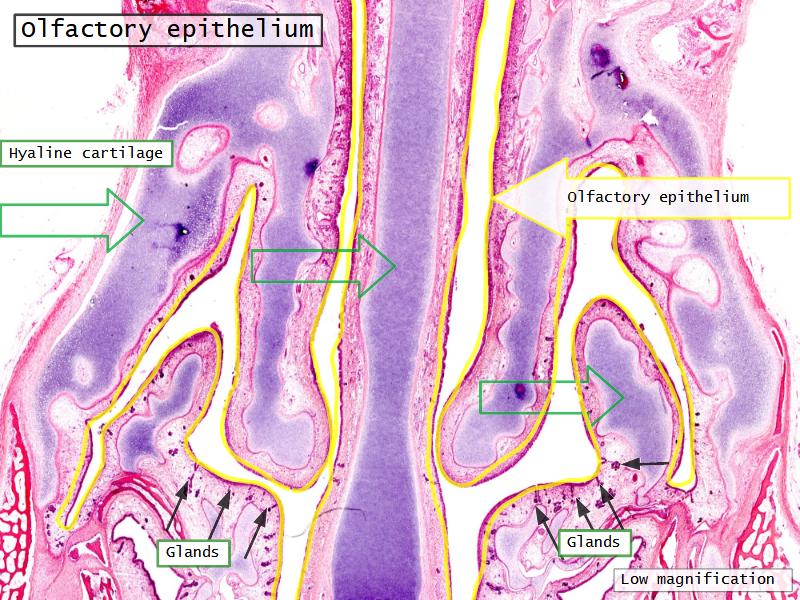

Function of the nasal cavity?

Function of the nasal cavity?

- Warm

- Moisture

- Filter

- Smell

Slides: Respiratory System

- Slide 108: Olfactory epithelium

Olfactory epithelium